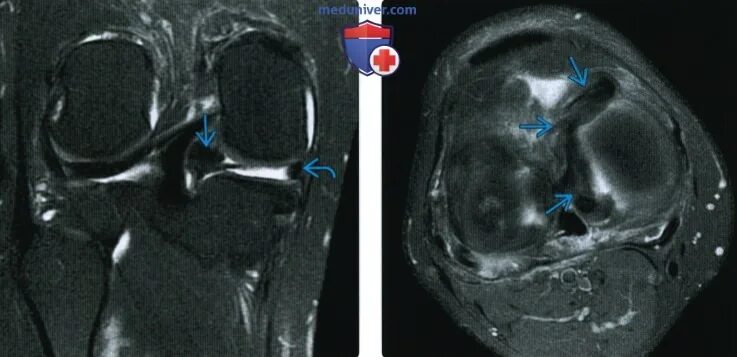

Stoller 3b разрыв